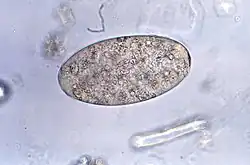

Fasciolopsis buski egg

Adults produce over 25,000 eggs every day; these take up to seven weeks to mature and hatch at 27–32 °C. Immature, unembryonated eggs are discharged into the intestine and stool. In two weeks, eggs become embryonated in water, and after about seven weeks, tiny parasitic organisms called miracidia hatch from the eggs, which then go on to invade a suitable snail intermediate host. Several species in the genera Segmentina and Hippeutis serve as intermediate hosts. In the snail the parasite undergoes several developmental stages (sporocysts, rediae, and cercariae). The cercariae are released from the snail and encyst as metacercariae on aquatic plants such as water chestnut, water caltrop, lotus, bamboo, and other edible plants. The mammalian final host becomes infected by ingesting metacercariae on the aquatic plants. After ingestion, the metacercariae encyst in the duodenum in about three months and attach to the intestinal wall. There they develop into adults (20 to 75 mm by 8 to 20 mm) in approximately three months, remaining attached to the intestinal wall of the mammalian hosts (humans and pigs). The adults have a life span of about one year.[7]

Examination of stool samples microscopically to identify parasite eggs can aid in the diagnosis of this parasite. However, due to intermittent egg shedding, multiple stool samples may be necessary for an accurate diagnosis. The WHO recommends the Kato-Katz technique as the method of choice for fascioliasis diagnosis attending to its ease of use and reproducibility, and its enhanced sensitivity compared with the observation of eggs in fresh faeces. Enzyme-linked immunosorbent assay (ELISA) or other serological tests can also help identify specific antibodies against Fasciolopsis buski antigens in the blood. In some cases, imaging techniques like ultrasound or endoscopy might also be used to visualize the flukes within the intestines.[8]